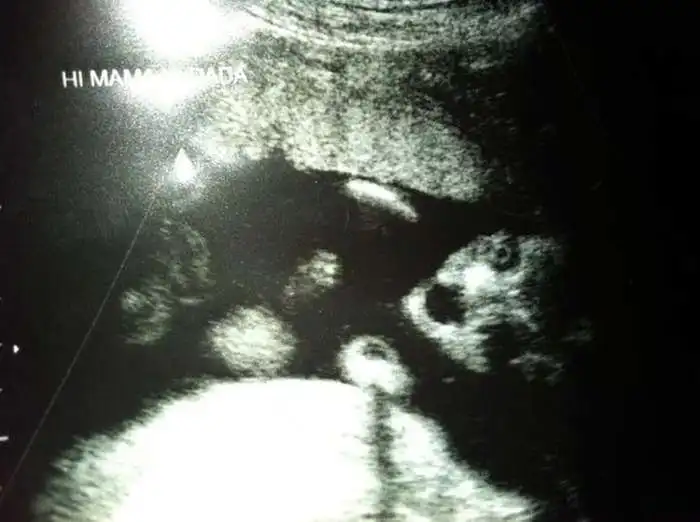

Как выглядят дети в утробе матери на экранах аппаратов УЗИ

На экранах аппаратов УЗИ дети, находящиеся в утробе матери, выглядят далеко не такими милыми и симпатичными, какими они оказываются после своего рождения.